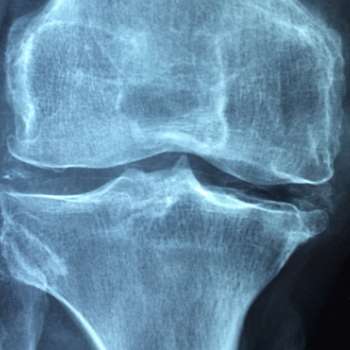

골다공증은 뼈의 밀도가 감소하고 뼈의 조직이 파괴되는 질환으로, 골절의 위험이 높아지는 상태입니다. 이 질환은 다양한 요인에 의해 발생할 수 있으며, 전문가적 입장에서 이러한 원인들을 살펴볼 수 있습니다.